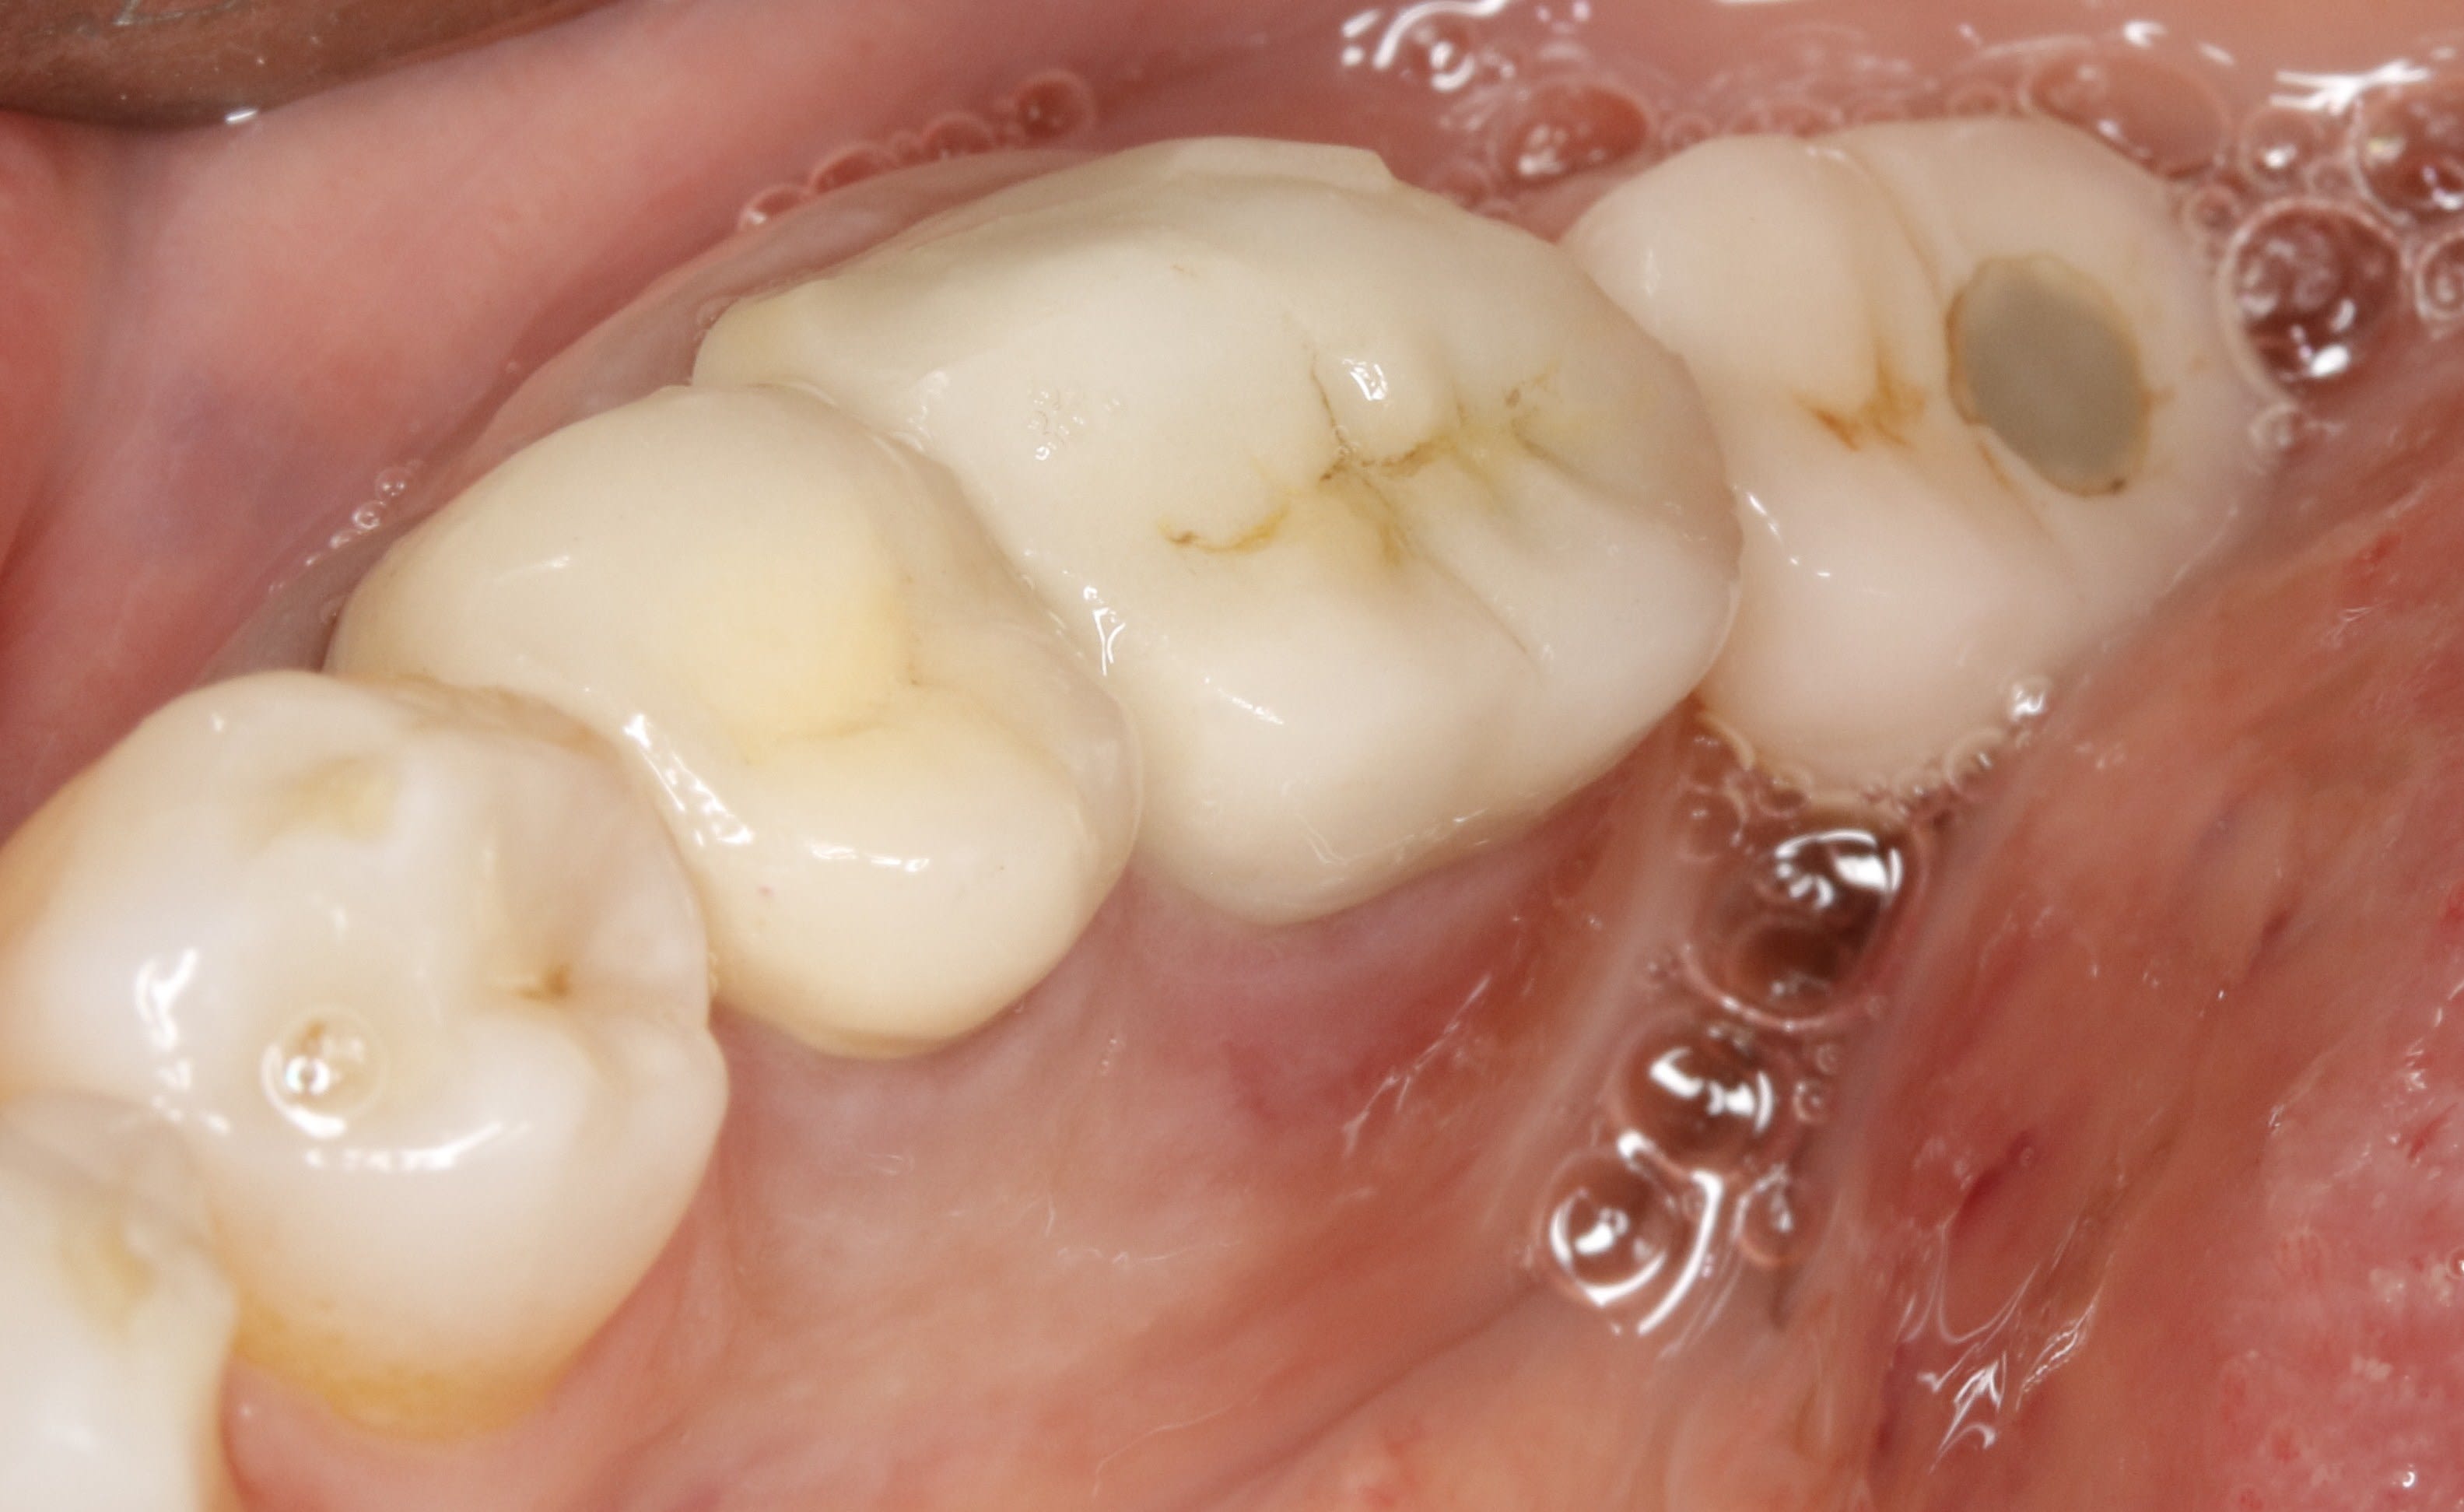

bon , bien , et si on regardais mon urgence , maintenant ?

( 15 mobile , la couronne bouge , fait mal , et fait clic clic quand on tire dessus . on lui a donné des AB il y a quelques jour )

ben voilà une belle perte de contact :-) fracture de l angle distal + mesialisation , comme de l autre coté ? a ben non pas mesialistion , pas possible

Je constate juste que la 13 est plus mesiale que la 23 sur l'arcade, comme si le bloc 13 14 15 s'était mesialé